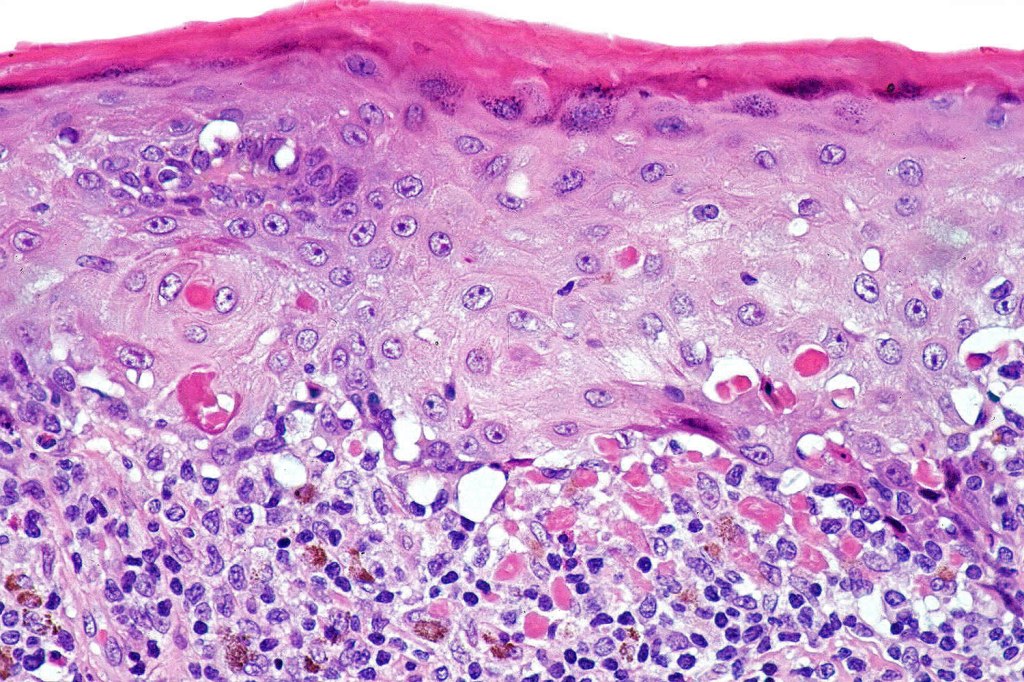

•Interface change

•Conspicuous cytoid bodies

•Pigment incontinence

. Late lesions are charcterized by epidermal atrophy, papillary dermal fibrosis, pigment incontinence & a perivascular or interstitial lymphocytic infiltrate